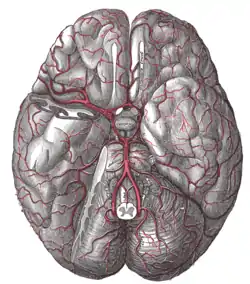

The arteries of the base of the brain.

In vertebrate anatomy, the pituitary gland, or hypophysis, is an endocrine gland, about the size of a pea and weighing 0.5 grams (0.018 oz) in humans. It is a protrusion off the bottom of the hypothalamus at the base of the brain. The hypophysis rests upon the hypophysial fossa of the sphenoid bone in the center of the middle cranial fossa and is surrounded by a small bony cavity (sella turcica) covered by a dural fold (diaphragma sellae).[2] The anterior pituitary (or adenohypophysis) is a lobe of the gland that regulates several physiological processes (including stress, growth, reproduction, and lactation). The intermediate lobe synthesizes and secretes melanocyte-stimulating hormone. The posterior pituitary (or neurohypophysis) is a lobe of the gland that is functionally connected to the hypothalamus by the median eminence via a small tube called the pituitary stalk (also called the infundibular stalk or the infundibulum).

| Artery | superior hypophyseal artery, infundibular artery, prechiasmal artery, inferior hypophyseal artery, capsular artery, artery of the inferior cavernous sinus[1] |